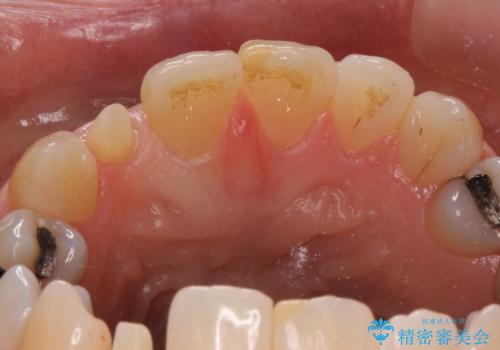

矮小(わいしょう)歯の形をセラミックで自然に 50代女性

- 右上の2番目の前歯がとがった形をしていたため、セラミックで形を整えています。

短くてとがった歯の形が反対側と同じ形となり、左右対称となり、ずいぶん自然な印象になりました。

下の前歯とのかみ合わせが切端咬合だったため、前歯の部分矯正も併せて行っています。(費用別途)